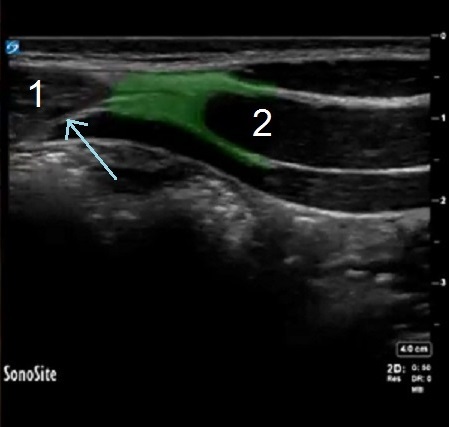

TAP Rectus Sheath Highlighted Image

Highlighted Area: Aponeurosis of the Internal Oblique Muscle

1. Rectus Muscle

2. Internal Oblique Muscle

Blue Arrow: Rectus Sheath